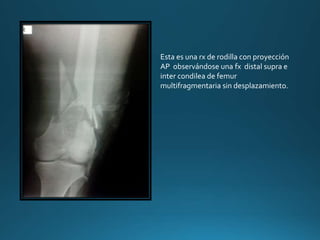

Esta es una rx de rodilla con proyección

AP observándose una fx distal supra e

inter condilea de femur

multifragmentaria sin desplazamiento.

LAT observándose una fx distal supra e

multifragmentaria con desplazamiento

posterior.